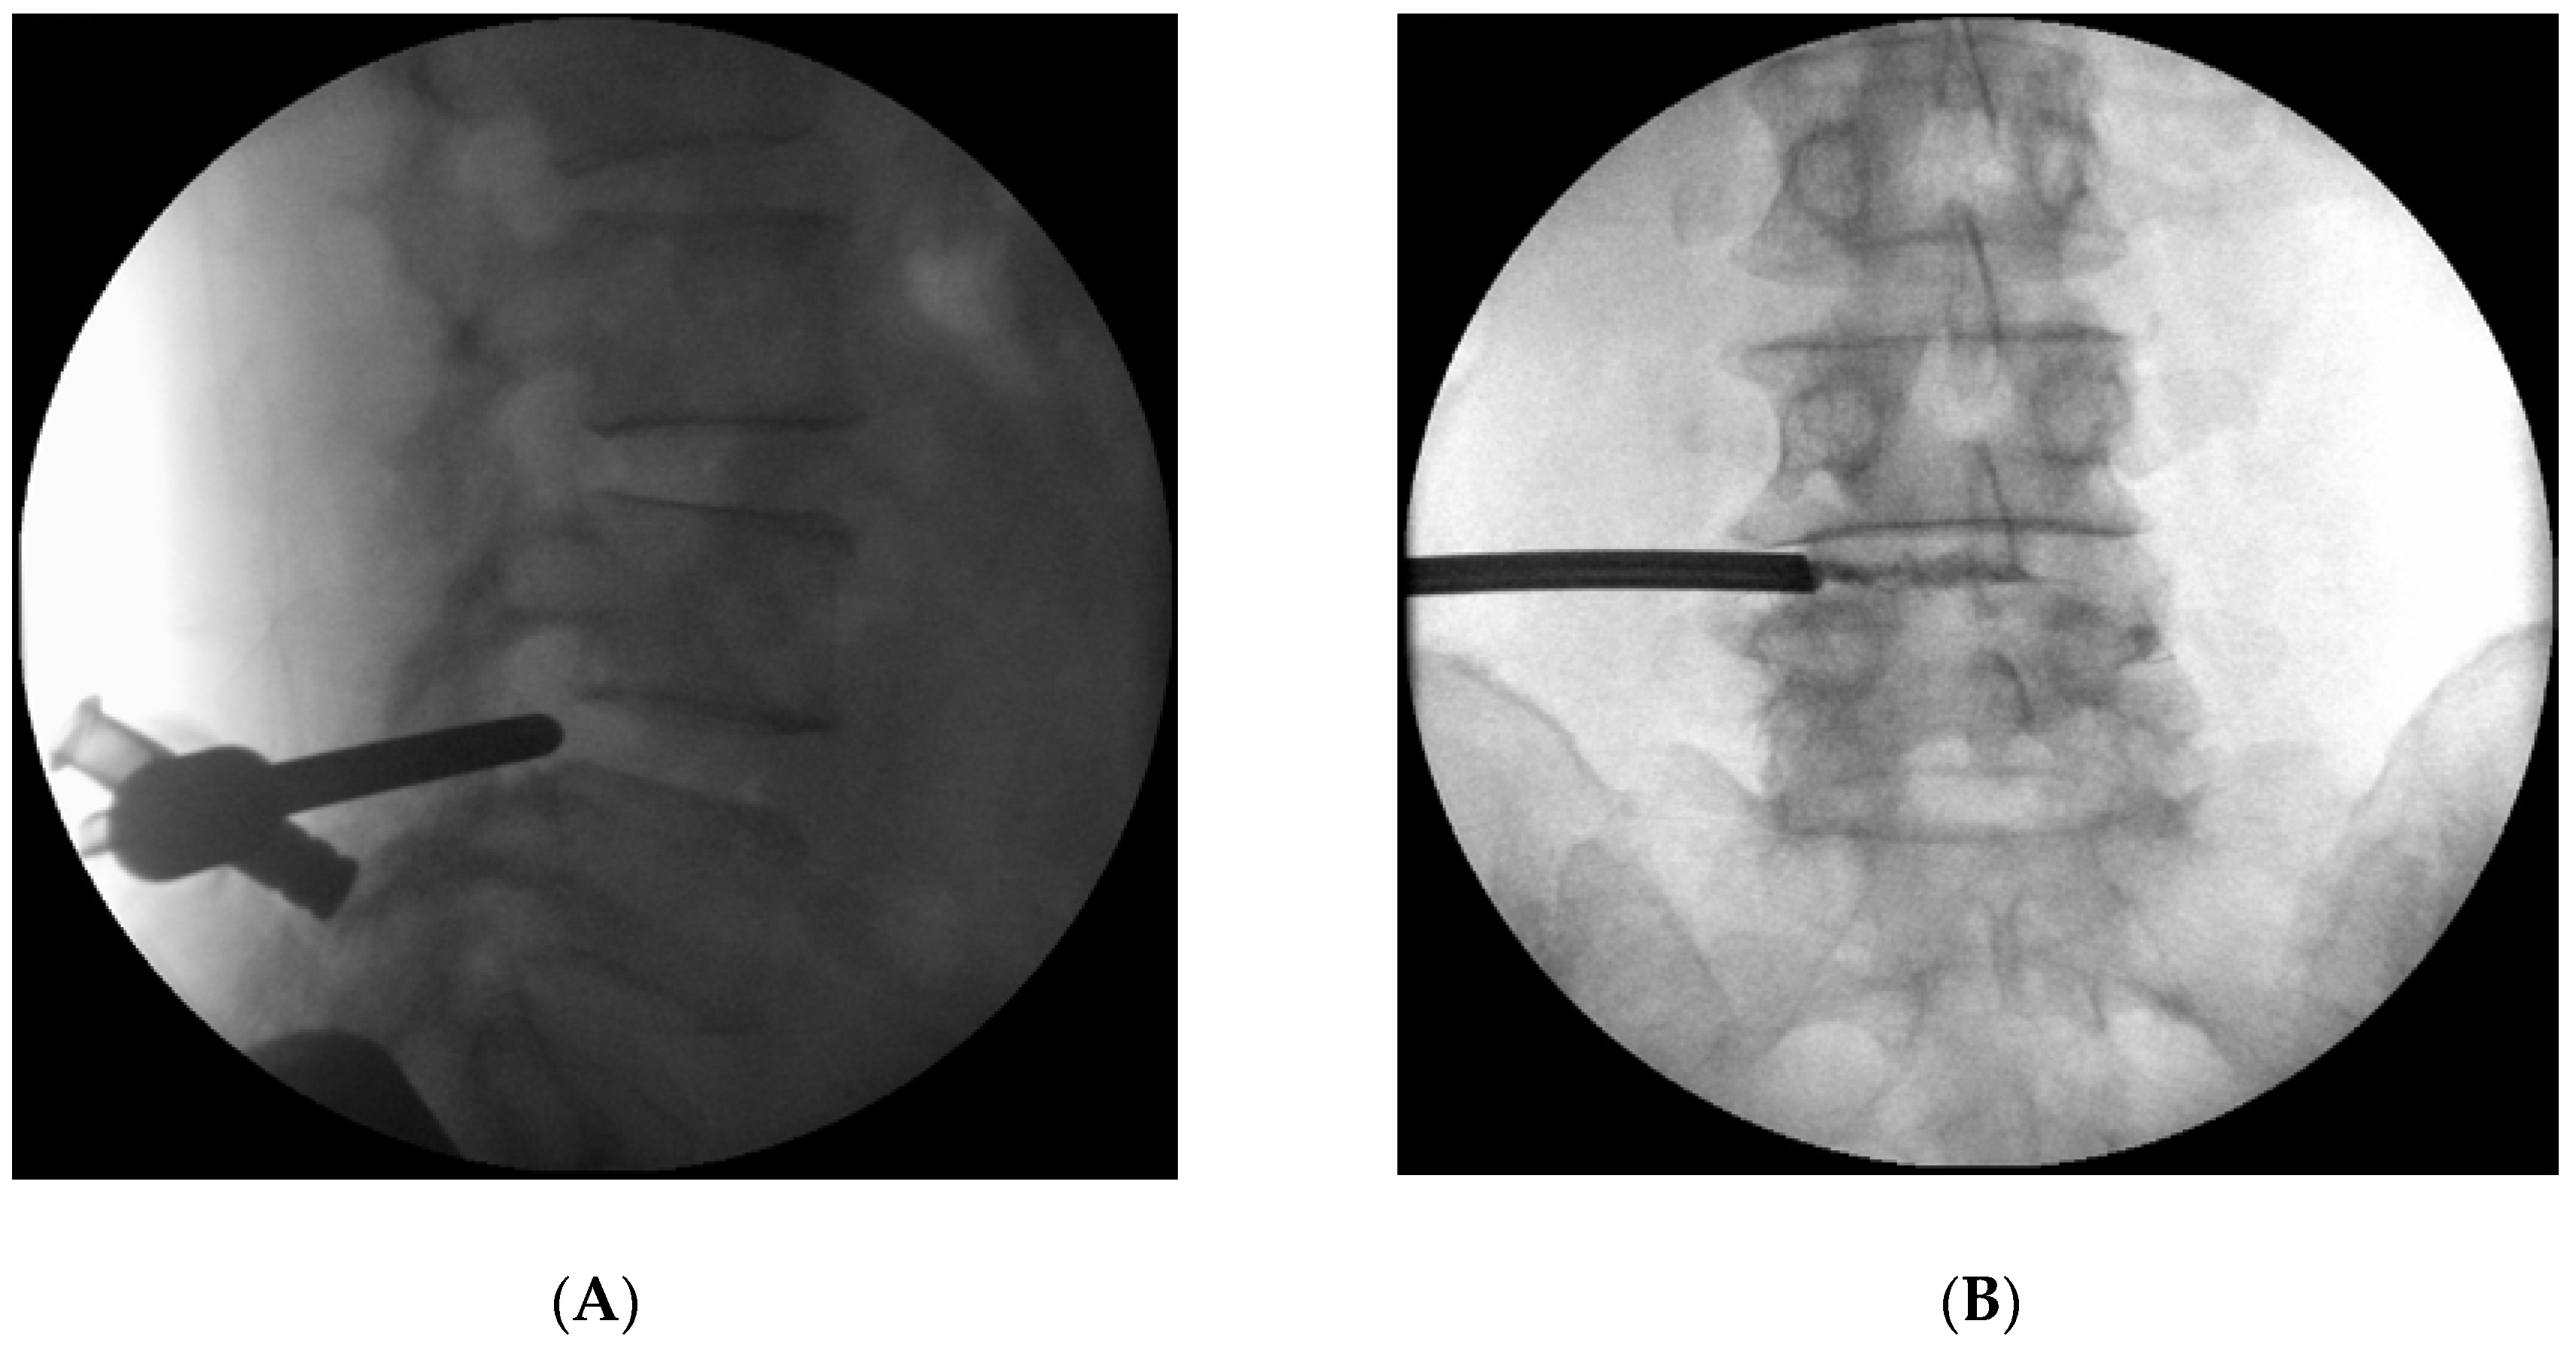

2. Case Report